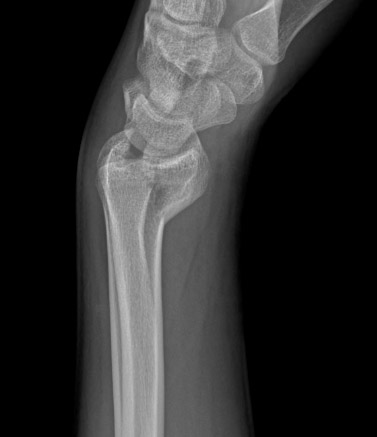

Type A extra-articular fracture of the distal radius: lateral view

From the collection of Dr Chaitanya S. Mudgal